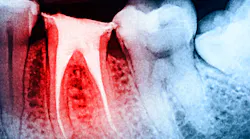

Teeth, especially multirooted teeth, can have more than one canal system. Canals that are hard to find or calcified can be missed, leading to pulp tissue that is not fully removed. In addition, teeth can have accessory canals that can be missed during root canal therapy, which can lead to posttreatment pain.4 Root and furcation perforations, irrigant irritation, filling material extrusion, and broken instrumentation in the canal system are all intraoperative problems that can lead to pain following a root canal. An examination by an endodontist may be necessary to diagnose these conditions.